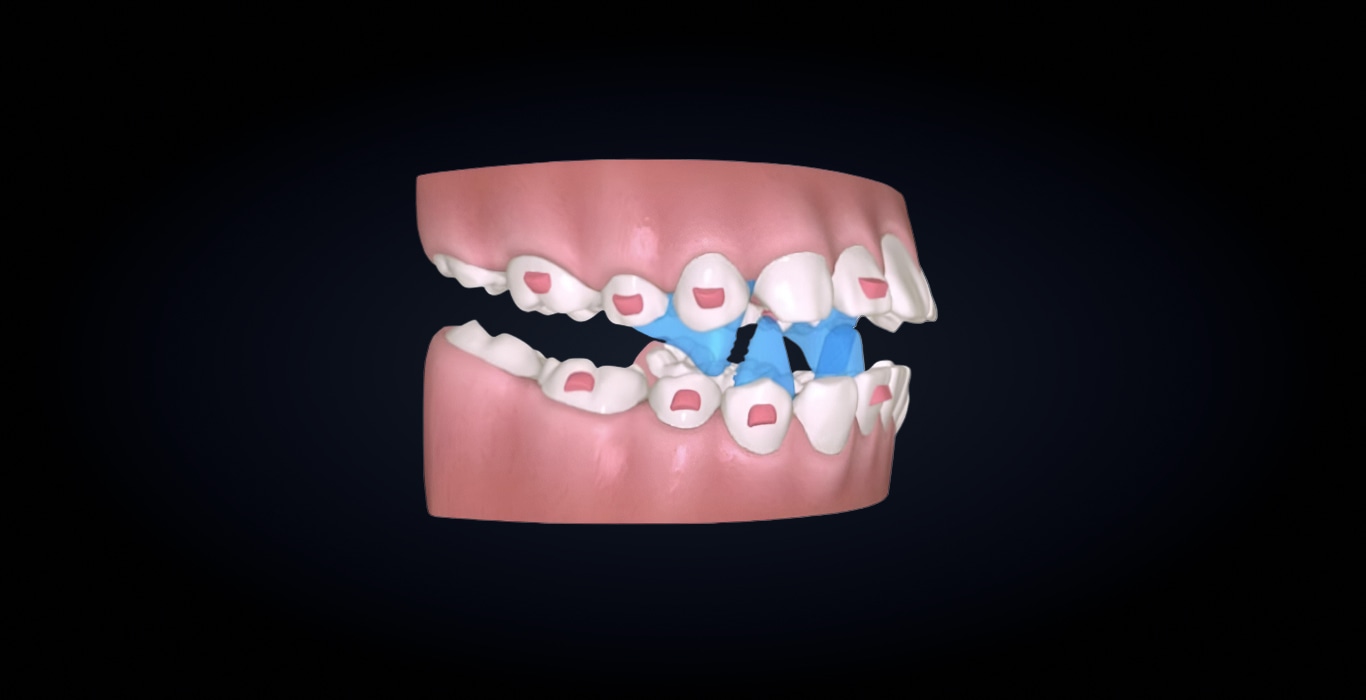

Объединяет в один процесс два этапа функционального ортодонтического лечения: выдвижение нижней челюсти и выравнивание зубов. Позволяет перемещать зубы и одновременно с этим корректировать окклюзионное соотношение, что повышает эффективность и сокращает длительность лечения.

Благодаря специально спроектированным окклюзионным блокам достигается контролируемое выдвижение нижней челюсти, а автоматизированный запрограммированный дизайн блоков исключает необходимость их коррекции вручную во время лечения.